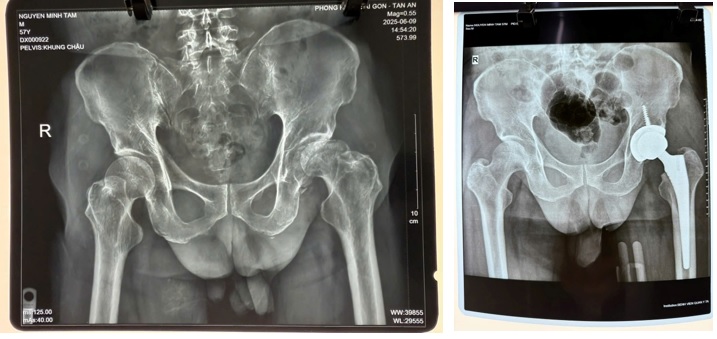

Trường hợp ông N.M.T, 57 tuổi, là ví dụ điển hình. Trước phẫu thuật, ông mô tả cảm giác "đi như kéo lê chân", thuốc giảm đau không còn tác dụng và ước vọng lớn nhất là có thể tự đi lại, tự lo sinh hoạt cá nhân mà không phụ thuộc người thân. Tuy vậy, bên cạnh kỳ vọng là những lo lắng rất thực tế: mổ có đau không, bao lâu mới đi lại được, liệu có biến chứng, phục hồi có hoàn toàn không?

Theo bác sỹ điều trị, trong trường hợp ông N.M.T, vết mổ dài khoảng 8-10 cm, cơ được tách nhẹ, không cắt, phẫu thuật diễn ra thuận lợi, ít mất máu, không cần truyền máu. Chỉ sau 24 giờ, bệnh nhân đã có thể đứng dậy và tập đi với hỗ trợ.

X-quang sau mổ cho thấy, khớp nhân tạo được đặt đúng vị trí, vết mổ khô và liền tốt sau một tuần, không ghi nhận biến chứng thần kinh hay nhiễm trùng.

Hình ảnh X-quang trước và sau mổ.